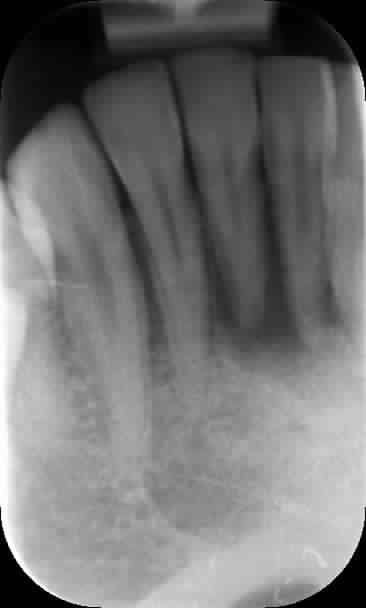

Quand même, un petit cas sympa endo-paro avec mobilités et fistule. Aujourd'hui, tout va bien : plus aucune sensibilité ni mobilité.

20/03/13, 24/04/13, 04/06/14